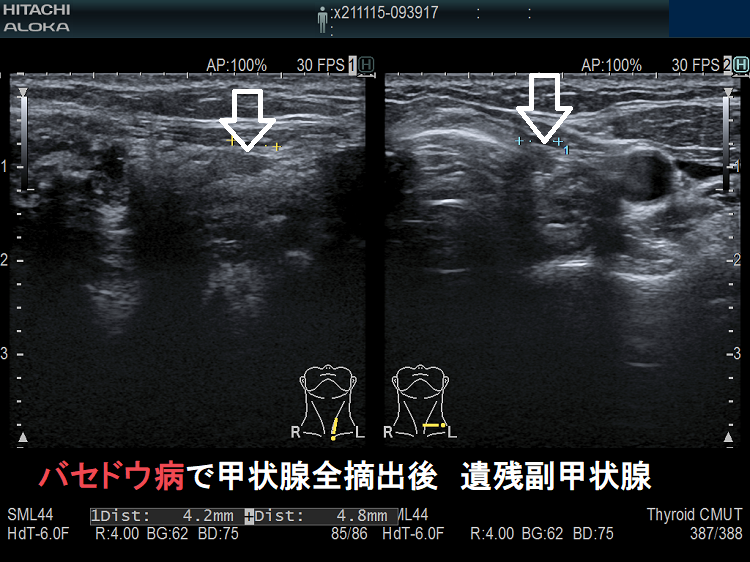

- 甲状腺摘術後、TSH 抑制療法;バセドウ病/甲状腺腫瘍で甲状腺切除と同時に副甲状腺も取ってしまった場合、取らずに温存した場合でも副甲状腺への血管を傷つけた場合

- 甲状腺全摘術時、副甲状腺も1-4腺を同時切除、あるいは切除しなくても栄養血管を損傷

- 甲状腺亜全摘術時、副甲状腺を数腺温存したつもりが、栄養血管を損傷

- 術後副甲状腺機能低下症による低カルシウム血症;術直後のみならず、10年~30年以上して著明な低カルシウム血症で発症する事もある(日腎会誌 2012;54(1):40-47.)(J Clin Diagn Res. 2017 Feb; 11(2): OD07–OD09.)。

ケース①

ケース②